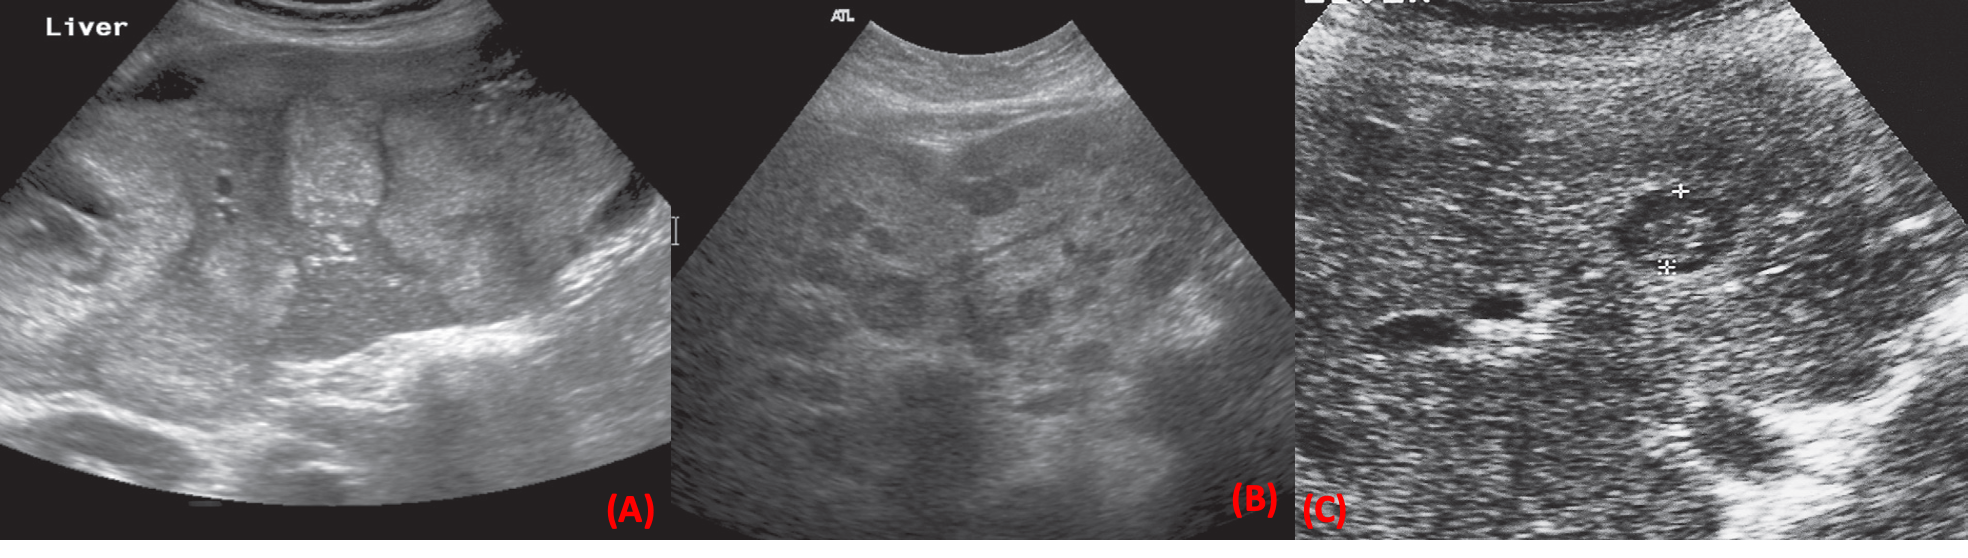

Ultrasound of liver metastases.

• (a) Multiple hyperechoic metastases scattered throughout the liver.

• (b) Multiple metastases appearing as well-defined, round, hypoechoic lesions scattered throughout the liver.

• (c) The cursors indicate a metastasis showing reduced echogenicity, but with an echogenic centre known as a target lesion; here is solitary lesion